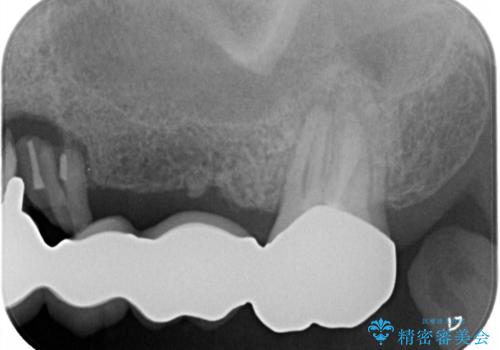

- 上の奥歯に装着されているブリッジが痛むとのことで来院された患者様です。

診察した結果、ブリッジの土台となっている歯が割れていたため、抜歯が必要となりました。

欠損している歯数が多いため、ブリッジによる補綴治療は困難と判断し、インプラントによる補綴治療を行うこととしました。

インプラントを埋入するために必要な骨の高さがなかったため、上顎洞底の粘膜を挙上しました。